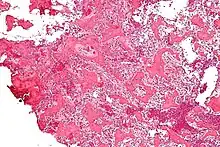

À l'examen histologique, l'ostéome ostéoïde présente :

- un petit (< 1,5–2 cm), nidus jaunâtre à rouge d'os tissé avec des trabécules interconnectées

- un fond et un bord de tissu conjonctif fibreux hautement vascularisé.

Des degrés variables de réaction osseuse sclérotique peuvent entourer la lésion. L'ostéoblastome bénin est pratiquement indiscernable de l'ostéome ostéoïde.

L'aspect habituel présente un stroma fibrovasculaire avec de nombreux ostéoblastes, du tissu ostéoïde, de l'os tissé bien formé et des cellules géantes. Les ostéoblastes étaient généralement petits et de forme régulière[2].